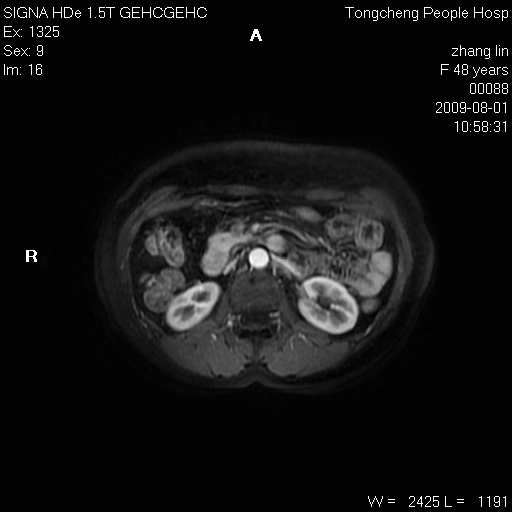

女,48岁。健康体检,彩超发现右肾占位性病变。平素健康。

临床诊断:右肾占位性病变,性质待定(囊肿?肿瘤?)。

上中腹部mr平扫+增强扫描,图像如下:

右肾上极见一类圆形病灶,t1wi呈等信号t2wi呈等高混杂信号,三期增强无强化,边界清---考虑囊肿出血。

同反相位均表现为等信号,病变无强化,考虑含蛋白的囊肿可能,弥散加权相或许有些帮助,